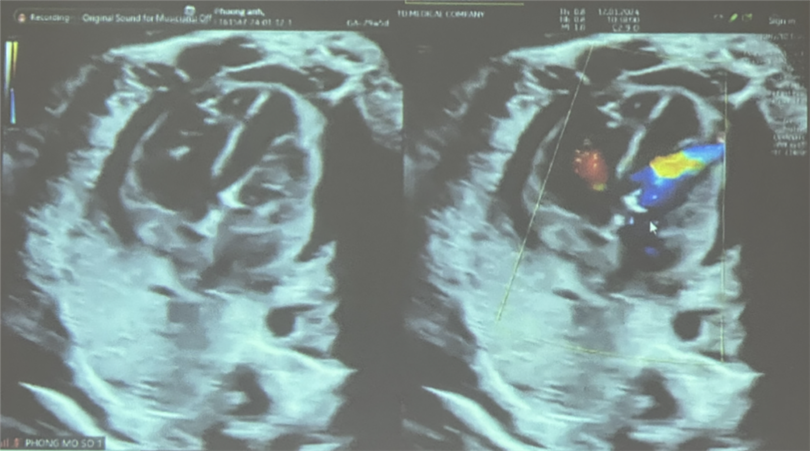

Siêu âm kiểm sau thực hiện can thiệp: luồng thông PFO shunt phải – trái, vận tốc qua van động mạch chủ 180 cm/s, không ghi nhận hở chủ

Đến ngày 11/1, thai được 29 tuần với diễn tiến hẹp van động mạch chủ nặng, đường kính van 2.6 mm, vận tốc máu qua van động mạch chủ 300cm/s, gây thiểu sản thất trái nặng hơn, trào ngược van 2 lá mức độ nặng.

Sau nong, kiểm tra dòng chảy qua van động mạch chủ lên tốt. Siêu âm kiểm sau thực hiện can thiệp, luồng thông PFO shunt phải – trái, vận tốc qua van động mạch chủ 180 cm/s, không ghi nhận hở chủ, nhịp tim thai 188 lần/phút, có tràn dịch màng ngoài tim nhẹ 4,5 mm.